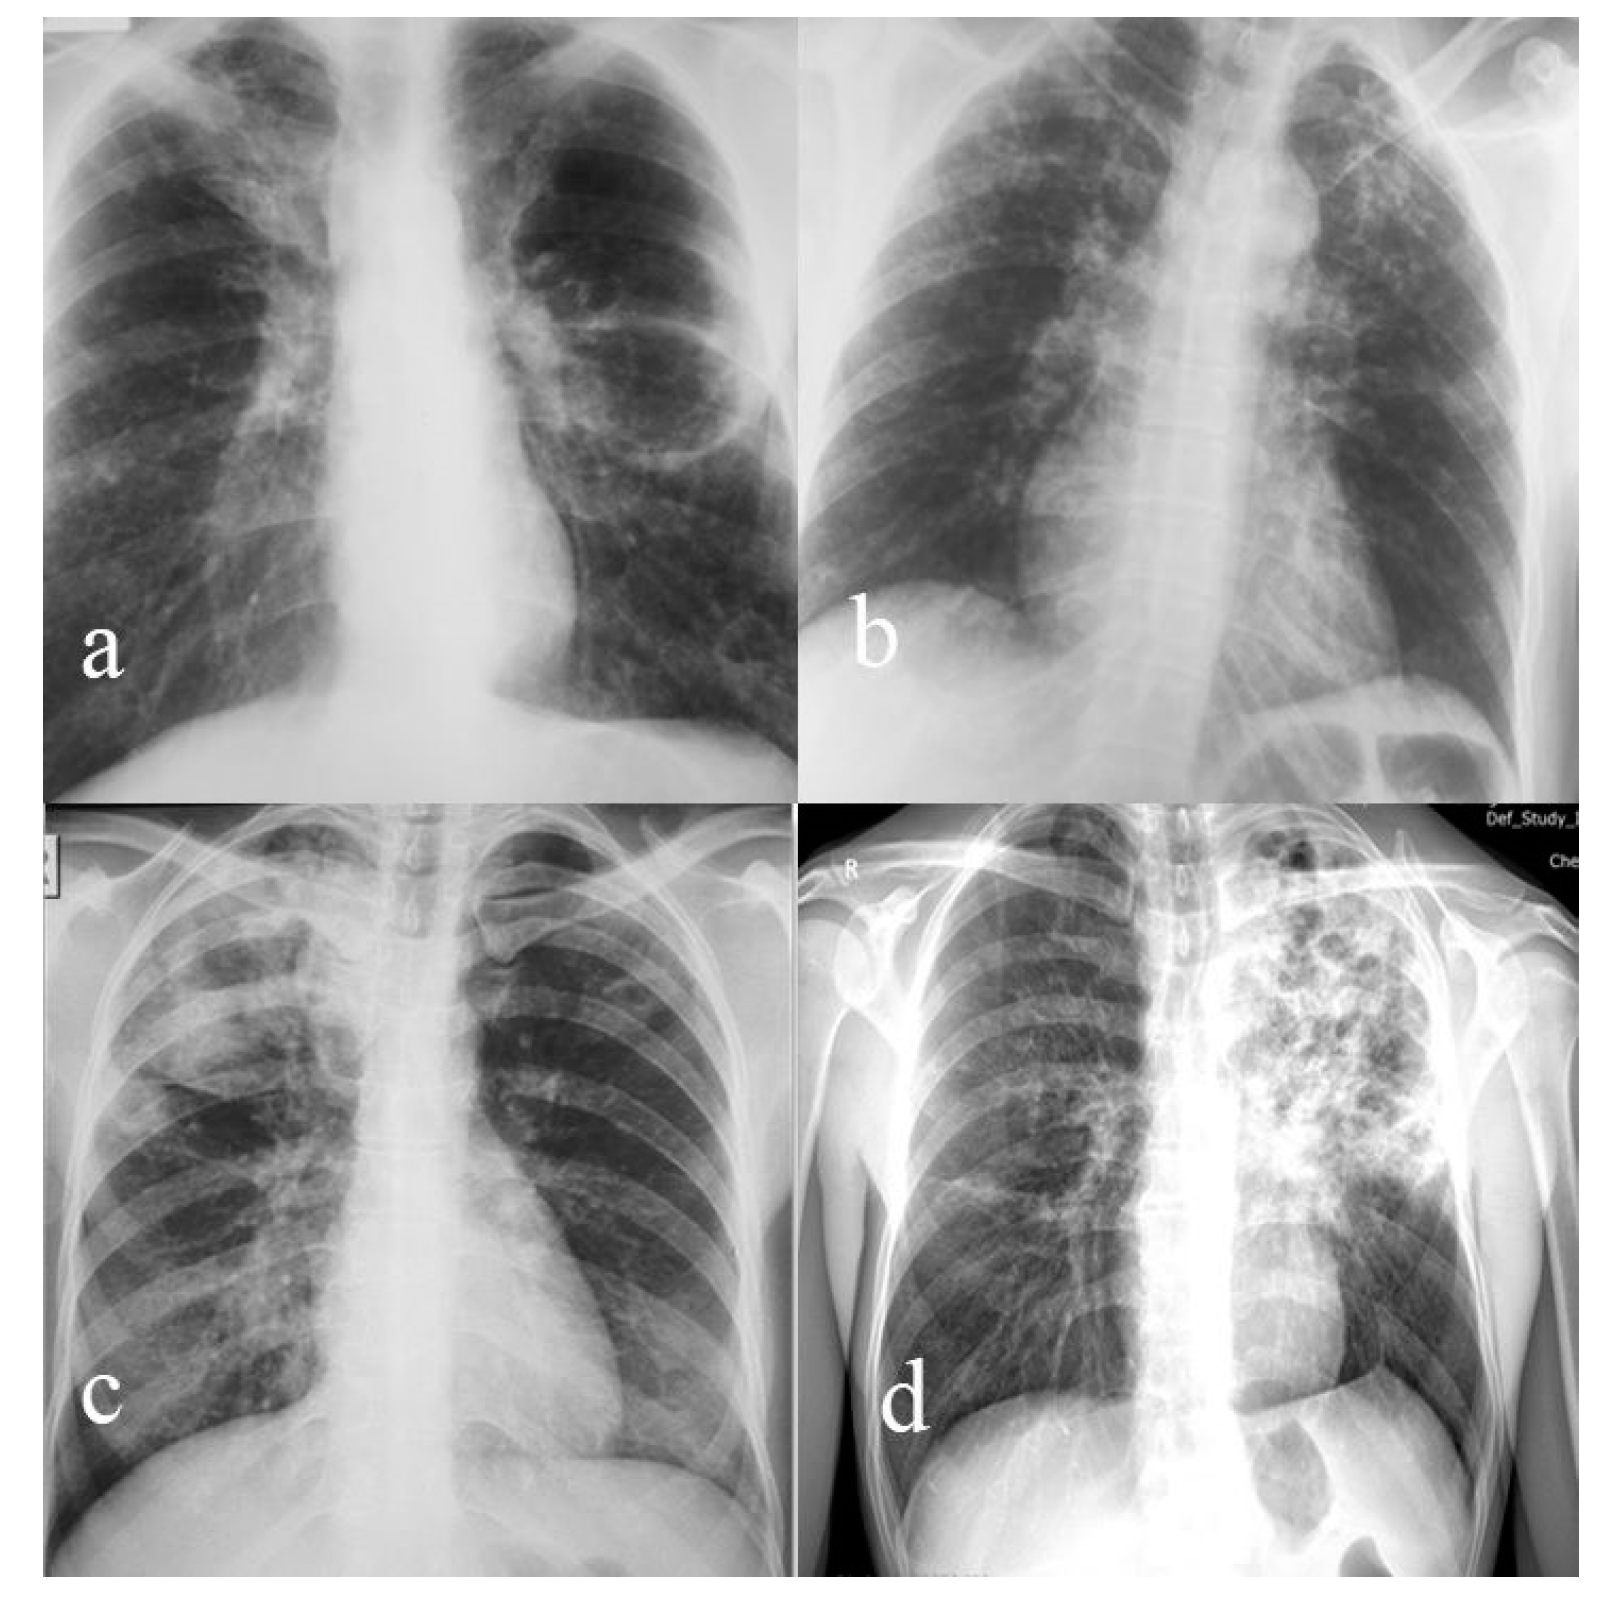

| Radiological presentation (Figure 1) | Nodular and caseous cavitary lesions | Bilateral apical ulcerated fibrocaseous lesions with bronchogenic disseminations | Caseous-cavitary lesions | Infiltrative nodular and bronchial forms |

| TB localization | Apical segment (Fowler) left lower lobe | Bilateral upper lobes | Right upper lobe | Left upper lobe |